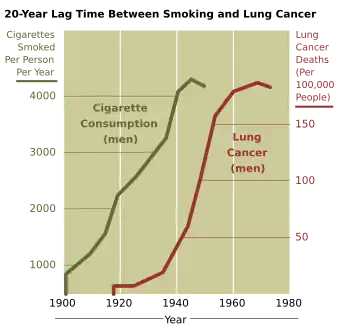

Tobacco is responsible for about one in five cancer deaths worldwide[54] and about one in three in the developed world.[55] Lung cancer death rates in the United States have mirrored smoking patterns, with increases in smoking followed by dramatic increases in lung cancer death rates and, more recently, decreases in smoking rates since the 1950s followed by decreases in lung cancer death rates in men since 1990.[56][57]